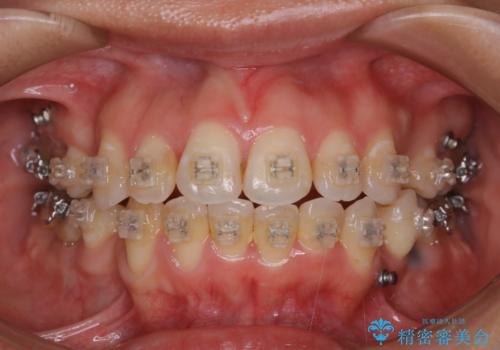

- 前歯の汚れが気になるため、綺麗にしたいとのことで来院されました。PMTC30分コースを行いました。